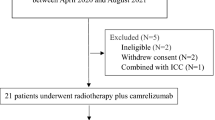

A prospective one-arm Phase I clinical trial was designed to evaluate the safety and efficacy of PBT followed by echo-guided direct intratumoral injection of a newly developed immunoadjuvant named “CalTUMP”, an HA adjuvant, in patients with HCC as illustrated in Figure 1. HA adjuvant dosage was increased incrementally as indicated in Table 1.

Treatment schedule. One treatment course comprises of proton beam radiotherapy (PBT) and 3 echo guided injections of CalTUMP every week. Delayed hypersensitivity test (DTH) using CalTUMP was performed 5–7 days after PBT. The first intratumoral injection of CalTUMP was performed 48 hours after DTH. The follow-up period was more than 1 year.